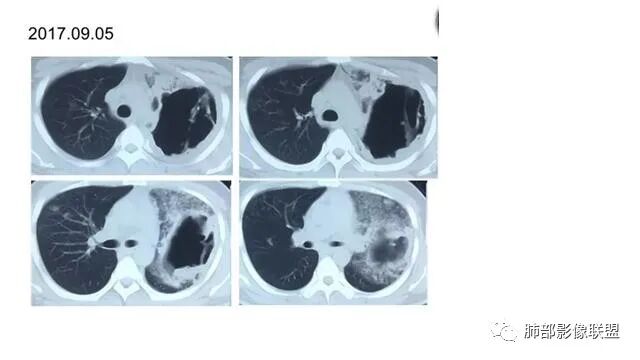

这些是坏死收缩形成的。空洞里面往往很干净,这个乳头凸起往往很光滑。毛霉是丝丝缕缕

曲霉,也只有慢性曲霉才会这样,急性形成不了这种光滑,必须是时间久,坏死彻底,有明显纤维化的修复才会如此。

你看,我发一组图片给你看

初学者:这个毛霉,壁是毛毛的,不。。。空洞壁内部不光滑的,里面丝丝拉拉的

包括曲霉,急性期也是丝丝拉拉的,但是慢性期,坏死物排空才可能光滑赶紧,这个人没有咯血。。

我慢慢给你发我手上所有的毛霉,你看。是完全不一样的。

毛霉因为嗜好血管,容易咯血,周围一般都是毛的。内壁也不会太光滑,里面也不会太干净

初学者:

随着时间。。他会慢慢变,但是内部还是那种很纤细的条索。。一般不会有乳头状突起

初学者:早期是这样的。。空洞之前。。是沿着支气管的毛玻璃。。

我发一个结核的空洞吧,你对照一下

吴老师的空洞对比图,你GET到了吗?